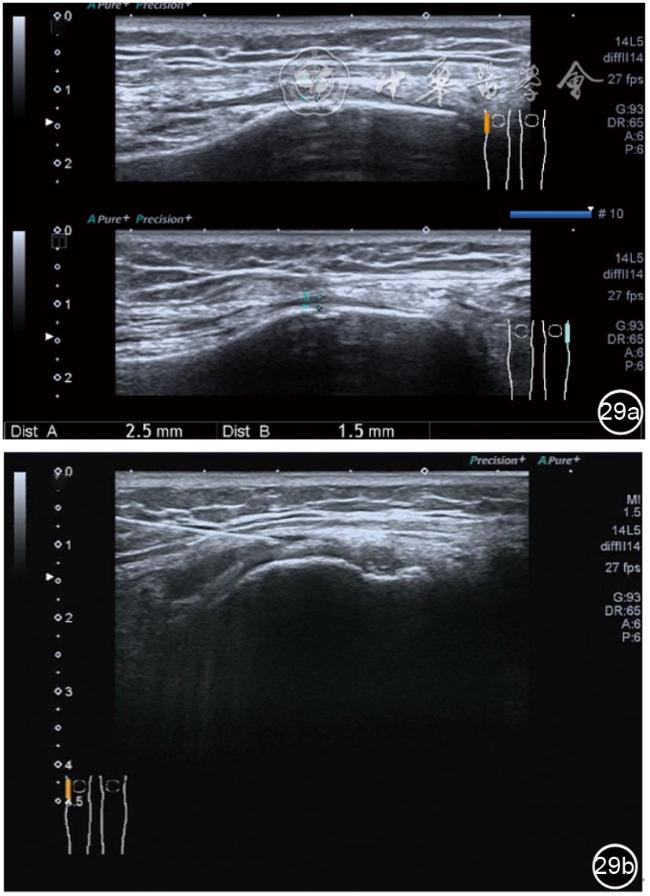

1.髂胫束局部治疗。仍以保守治疗为首选。如物理治疗、口服药物、康复训练等,早期可以超声引导下肌腱表面注射治疗。针刀剥离松解治疗具有创伤小、恢复时间短、感染率低、适应证广,无绝对禁忌证等优势,可作为首选手术方案。(1)髂胫束胫骨附着点表面局部药物注射治疗。患者侧卧位,髋内旋,膝关节屈曲20°~30°,膝下垫枕。局部消毒,铺无菌巾,穿刺区域常规消毒,探头涂抹耦合剂后套入无菌手套碘伏消毒或使用无菌耦合剂,长轴显示髂胫束,找到胫骨附着点病变部位。选用25G针头,抽取1%利多卡因3 ml+曲安奈德10 mg,超声引导下针尖到达肌腱表面进行注射(图28),注射完毕拔出针头,局部压迫2分钟,穿刺点创可贴覆盖。(2)髂胫束股骨外髁附着点局部药物注射治疗。体位及治疗前准备同髂胫束胫骨附着点表面局部药物注射治疗,长轴显示髂胫束,找到股骨外髁附着点病变部位。确定髂胫束与股骨外髁之间为靶点,选用25G针头,抽取1%利多卡因3 ml+曲安奈德10 mg,超声引导下,针尖到达骨表面进行注射(图29),注射完毕拔出针头,局部压迫2分钟,穿刺点创可贴覆盖。(3)髂胫束胫骨附着点局部针刀剥离松解治疗。体位及治疗前准备同髂胫束胫骨附着点表面局部药物注射治疗。超声探头长轴位扫查,根据压痛点和超声显示肌腱变化的位置确定靶点。用1%利多卡因3 ml沿韧带表面及胫骨止点病变部位局部麻醉。选用直径0.6 mm的Ⅰ型2号针刀由近端向远端平面内进刀,平刀在韧带表面剥离松解3~5刀,然后进入胫骨附着点损伤处进行剥离松解3~4刀拔出针刀(图30),局部压迫止血5分钟,无菌敷料覆盖。(4)髂胫束股骨外髁附着点局部针刀剥离松解治疗。体位及治疗前准备同髂胫束胫骨附着点表面局部药物注射治疗。超声探头长轴位扫查,根据压痛点和超声显示肌腱变化的位置确定靶点。用1%利多卡因3 ml沿股骨外髁部位的髂胫束表面局部麻醉。选用直径0.6 mm的Ⅰ型2号针刀由近端向远端平面内进刀,平刀在髂胫束表面剥离松解3~5刀拔出针刀(图31),局部压迫止血5分钟,无菌敷料覆盖。

图29 超声引导下髂胫束股骨外髁附着点局部药物注射治疗